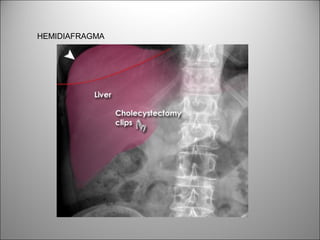

HIPOCONDRIO DERECHO

HEMIDIAFRAGMA

BASES PULMONARES